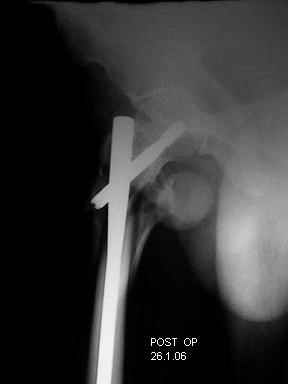

I choose Long Gamma Nailing and did it on 24.1.2006.

Now posting the post op x-rays for all of yours comments please. Don't hesitate to criticize me.